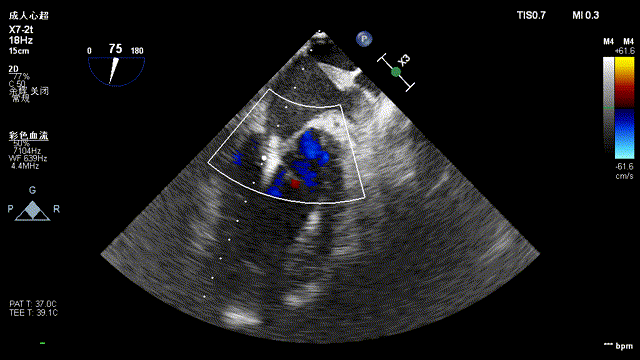

经心尖TAVR

主动脉根部造影后,介入器跨瓣:

定位件进入窦部:

将瓣膜件降至合适水平面:

释放瓣膜后,复查根部造影,未见明显反流,瓣膜形态和位置满意,双侧冠脉显影良好:

复查超声显示主动脉瓣架深度合适、位置稳定,瓣叶启闭正常,未见明显瓣周反流: